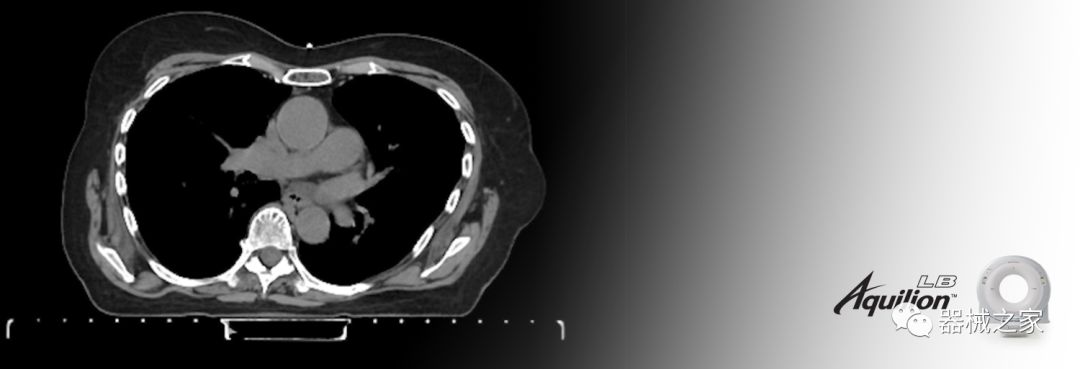

Aquilion LB專為滿足腫瘤學(xué)挑戰(zhàn)而設(shè)計,同時優(yōu)先考慮患者護(hù)理。Aquilion LB的內(nèi)徑為90 cm,能夠幫助復(fù)雜的患者設(shè)置并提高患者的舒適度。CT模擬定位可以輕松鏡像放射治療定位,更加自信。該系統(tǒng)采用0.5 mm x 16排(32層)PUREViSION探測器技術(shù),70 cm視野,AIDR 3D和SEMAR技術(shù)。